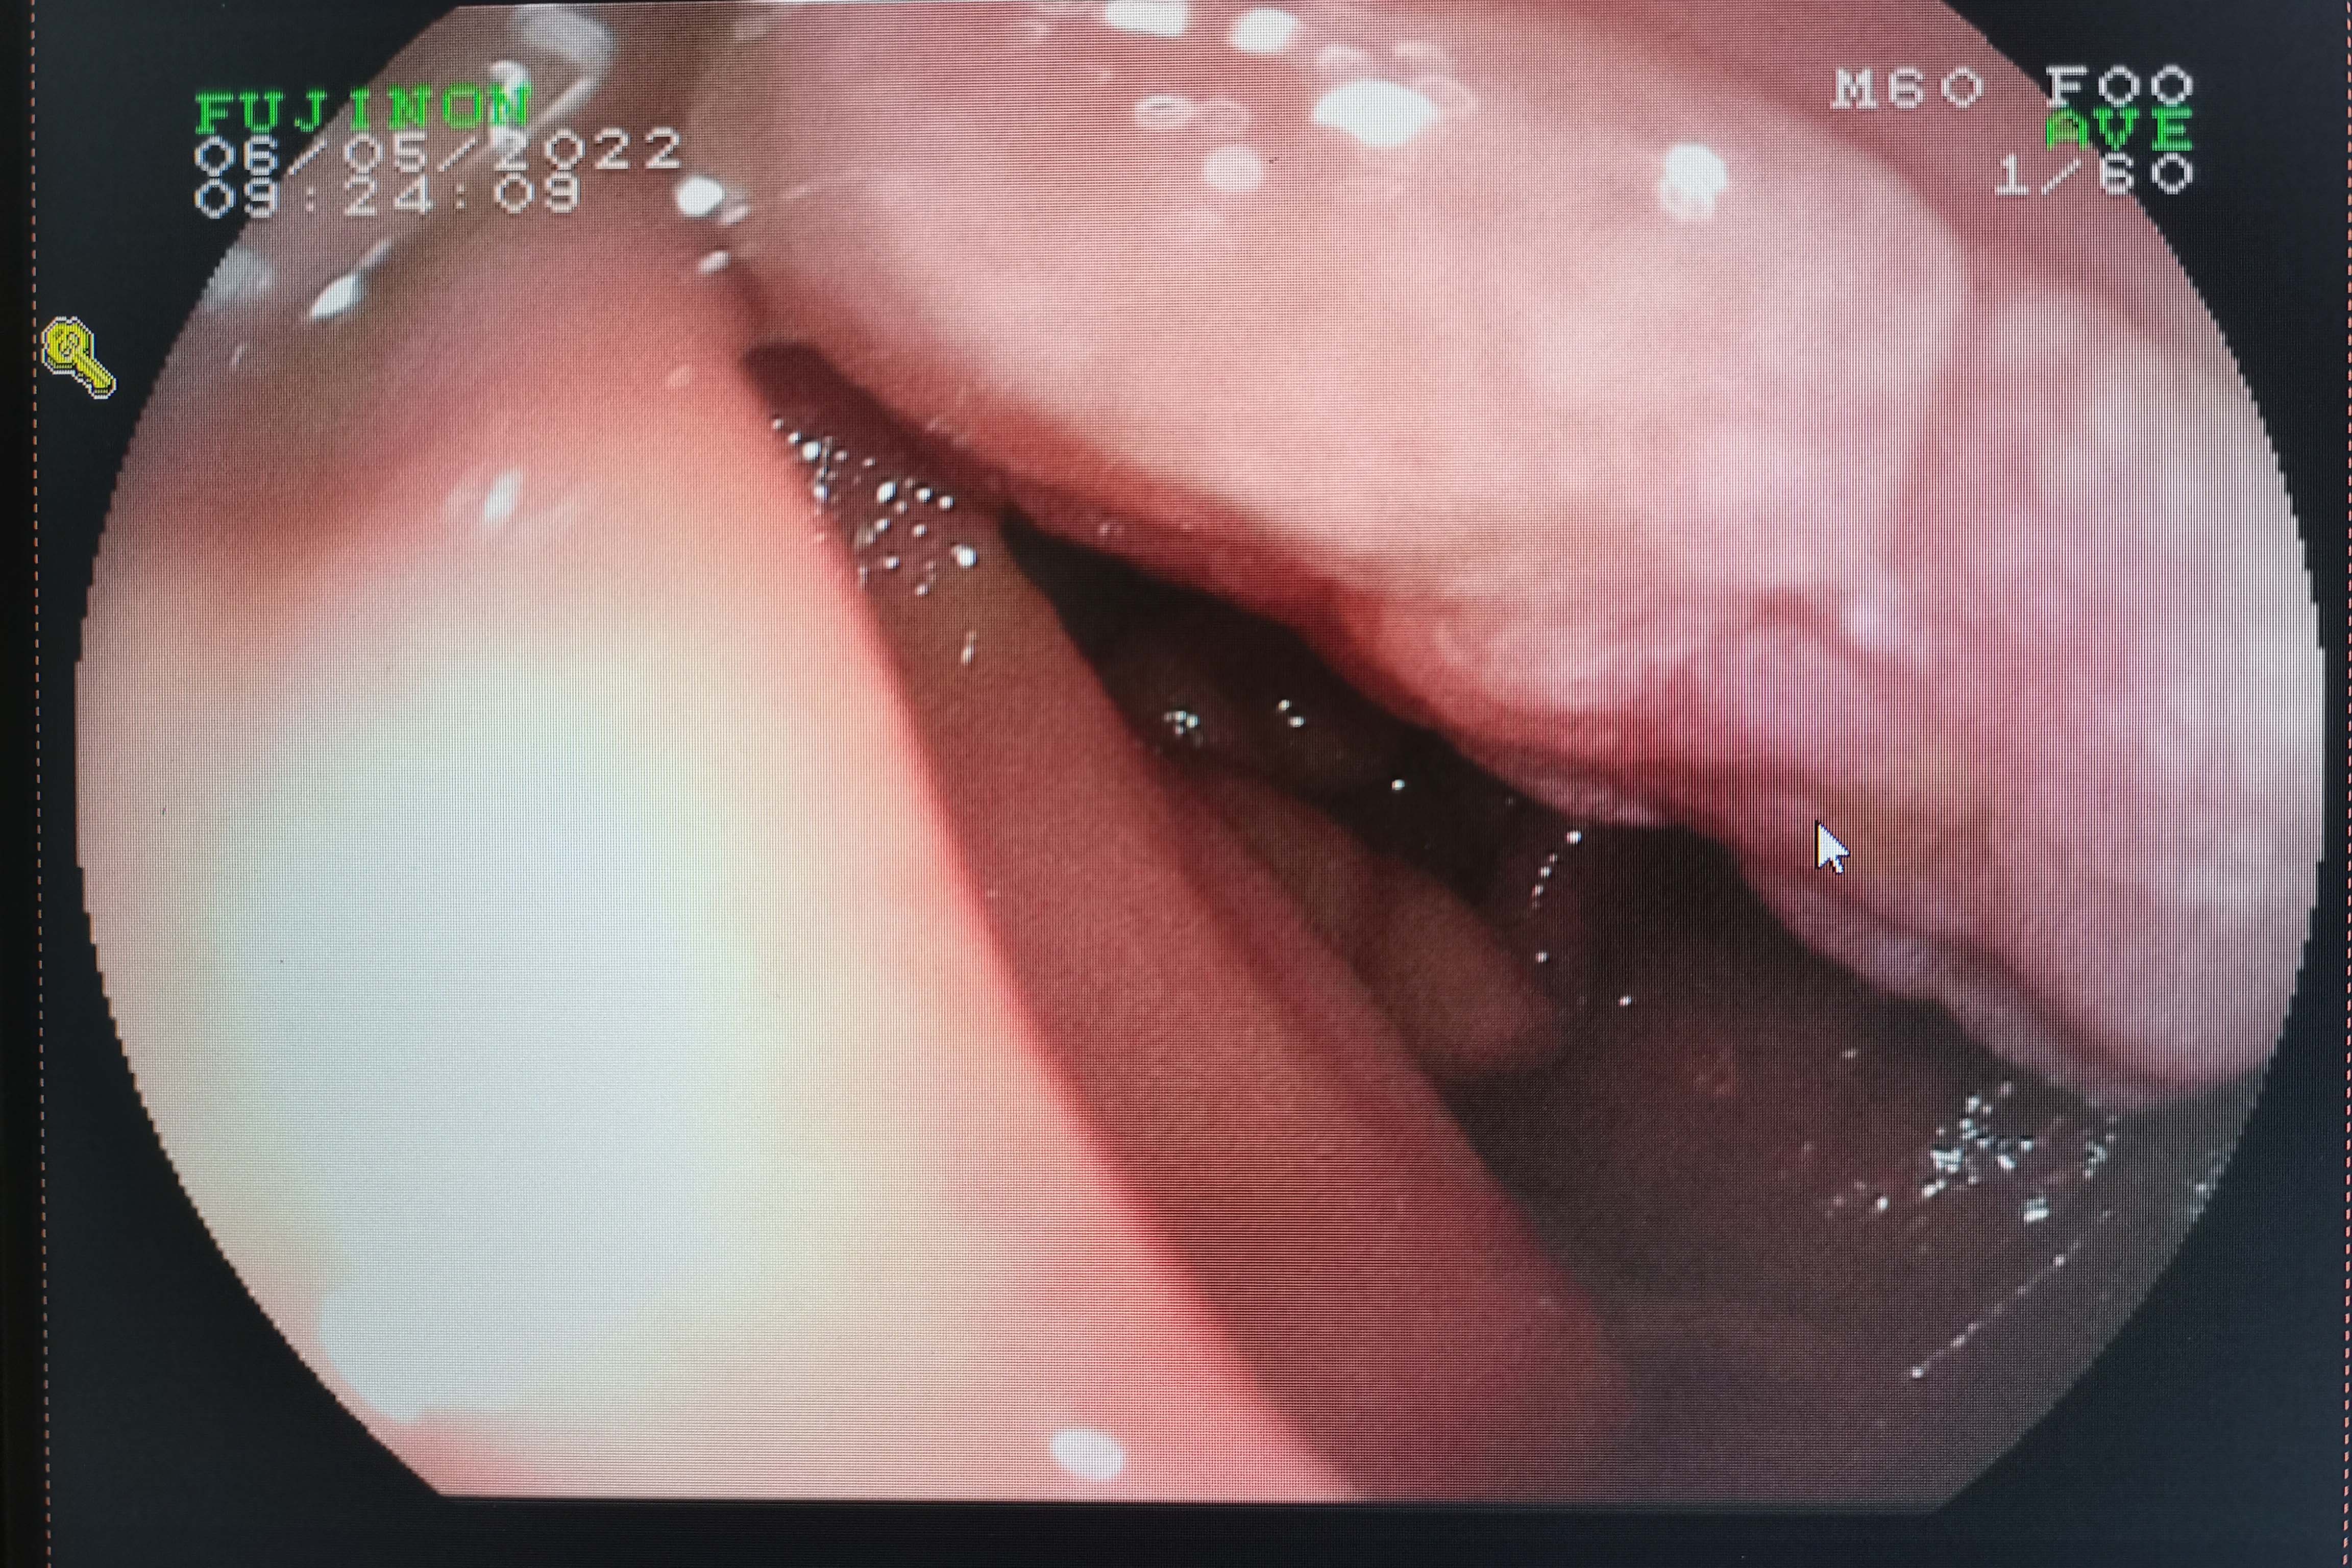

入院后查血提示肝功能异常,胆红素高达122.1 umol/L。腹部增强CT、增强MR+MRCP均提示:胆总管下段、十二指肠乳头区占位,考虑壶腹癌;低位胆道梗阻,肝内外胆管、胰管扩张。行胃十二指肠镜检查示:十二指肠降段肿物。这些检查结果显示:患者的黄疸症状为壶腹部肿瘤压迫堵塞胆管,胆汁流出受阻所致。